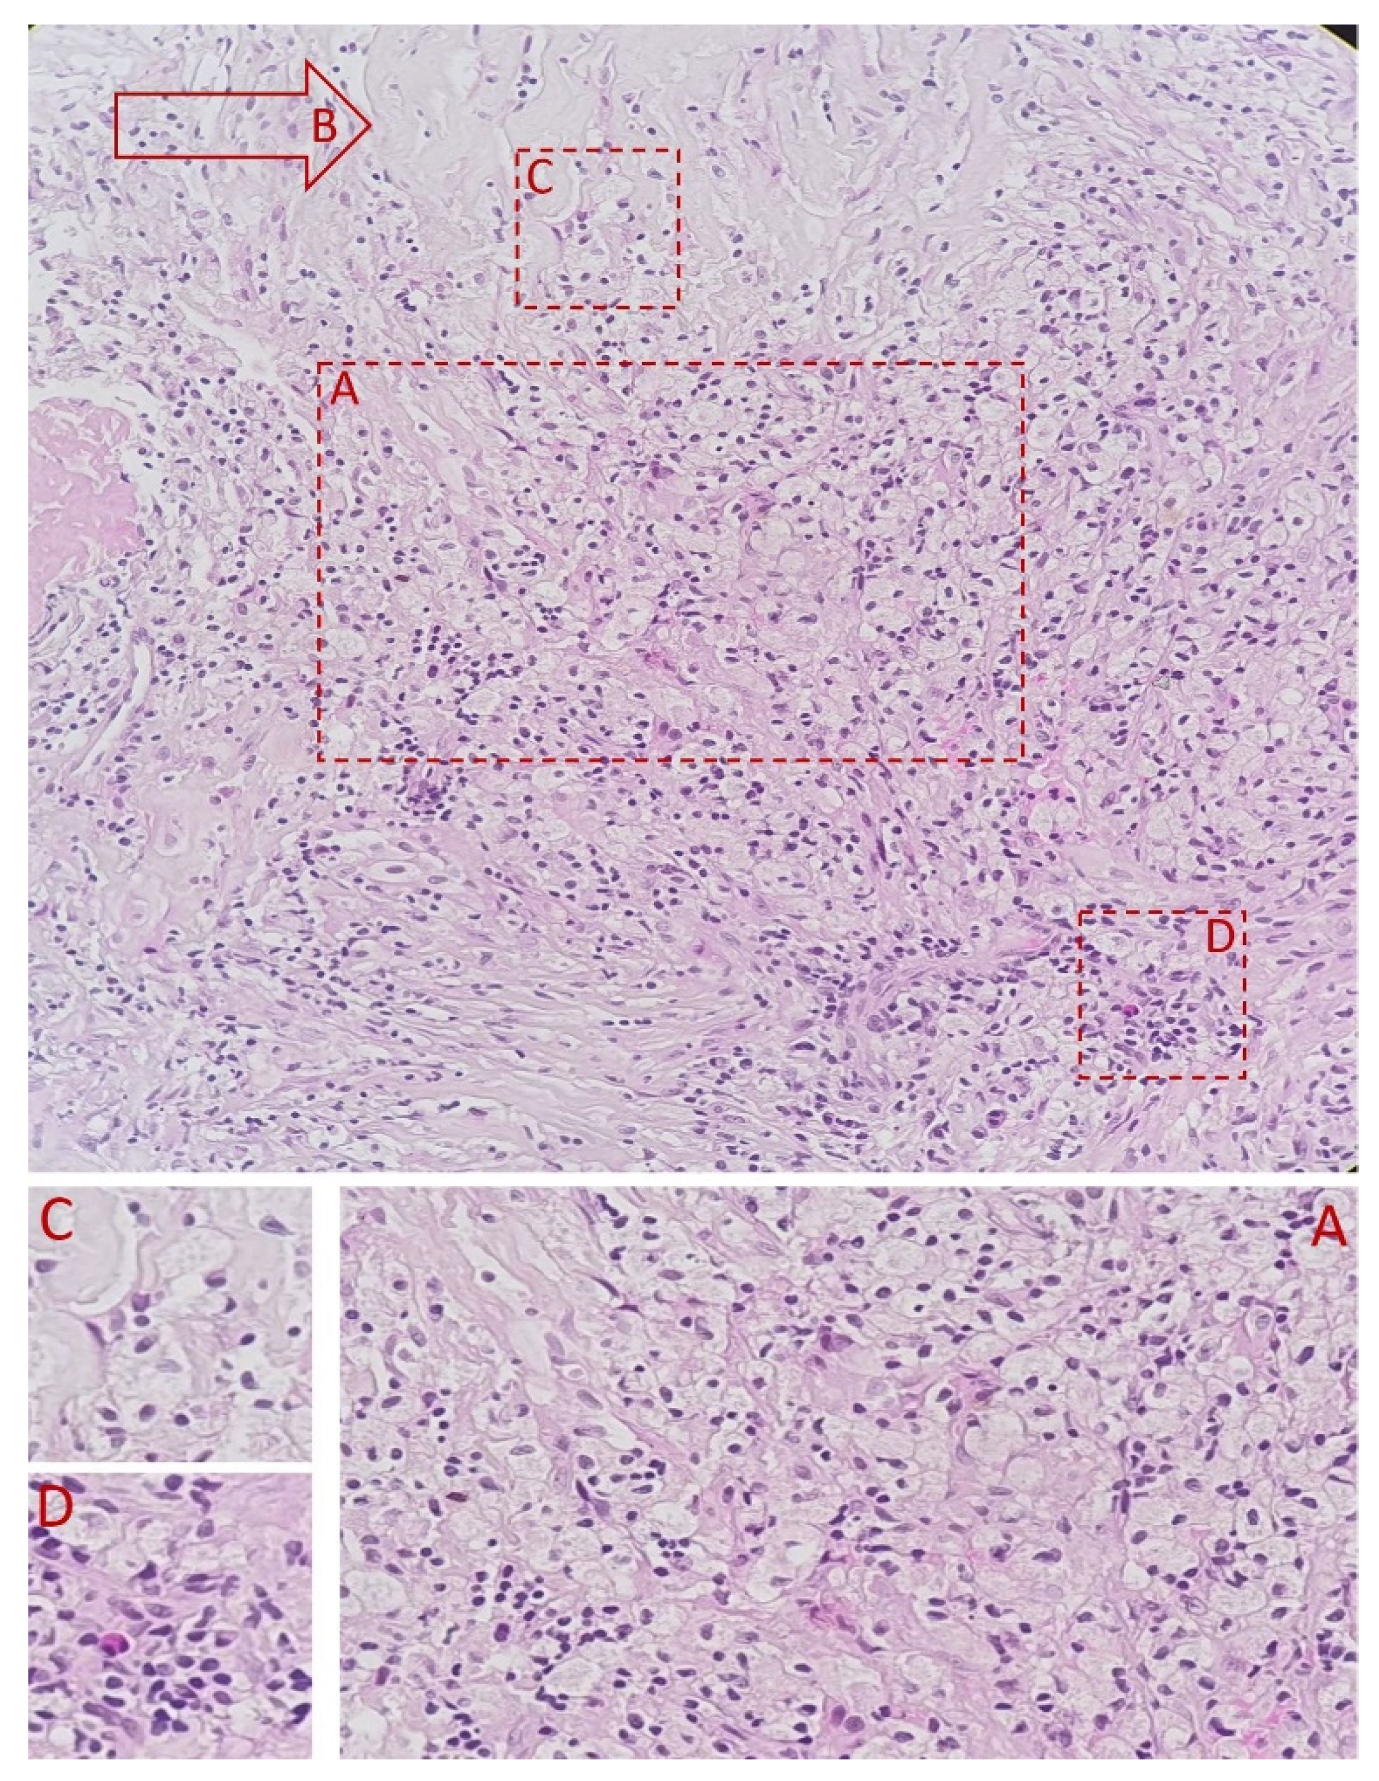

3.2. Histopathological Examination of the Specimen